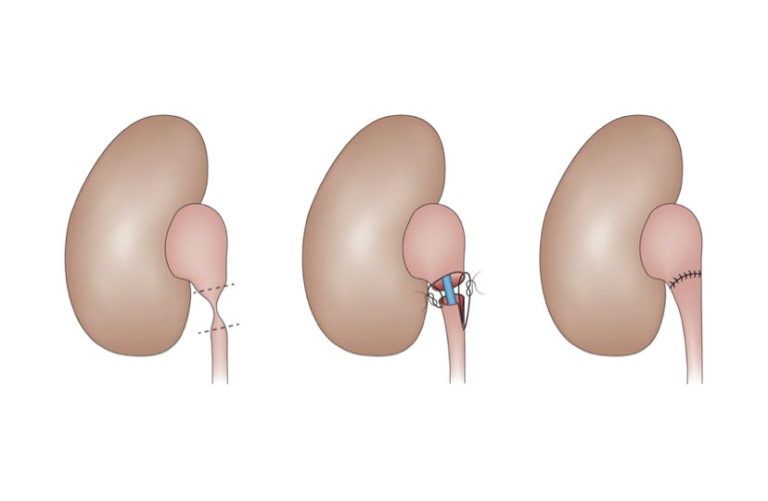

PIELOPLASTIA ROBÓTICA

É uma cirurgia minimante invasiva para o tratamento de estreitamentos (estenoses) do ureter, que é a estrutura por onde a urina passa do rim até a bexiga.

Seja congênita ou adquirida, a estenose de ureter pode levar a perda total da função renal se não corrigida a tempo

É uma cirurgia minimante invasiva para o tratamento de estreitamentos (estenoses) do ureter, que é a estrutura por onde a urina passa do rim até a bexiga.

Seja congênita ou adquirida, a estenose de ureter pode levar a perda total da função renal se não corrigida a tempo